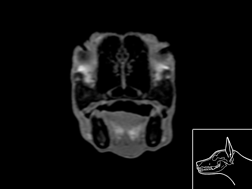

Atlas cérébral du chien IRMT1

IRM T1

>> 17 coupes